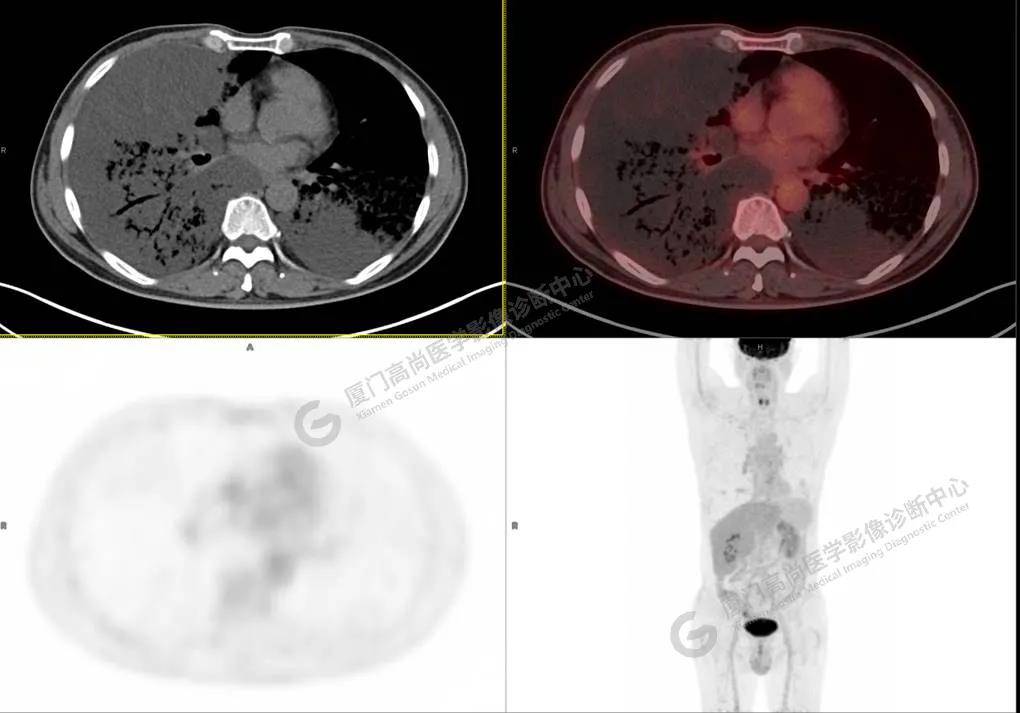

PET/CT影像圖

圖3

PET/CT所見(jiàn):雙肺大片實(shí)變影及磨玻璃影,部分呈地圖樣改變,累及右肺尖,部分放射性攝取輕微增高,SUVmax 1.77,其內(nèi)見(jiàn)多發(fā)支氣管充氣征象。

影像診斷: 雙肺大片實(shí)變影及磨玻璃影,大部分代謝不高,局部代謝輕微增高,考慮肺泡蛋白沉積癥,建議病理學(xué)檢查或肺泡灌洗物檢查。

影像學(xué)表現(xiàn):HRCT上雙肺斑片影,以肺門為中心呈蝶翼狀對(duì)稱分布;病變可隨機(jī)分布在中央?yún)^(qū)、周圍區(qū)或全肺葉,病灶與正常分組織分界清楚,呈典型“地圖樣”改變;有支氣管充氣征,但表現(xiàn)為充氣支氣管細(xì)小且數(shù)量及分布稀少;“碎石路”征由彌漫性磨玻璃影及內(nèi)部網(wǎng)格樣小葉間隔增厚組成(鋪路石樣表現(xiàn))。無(wú)空洞、蜂窩狀改變、淋巴結(jié)腫大、胸腔積液及明顯實(shí)變等。肺內(nèi)病灶累及范圍、磨玻璃密度高低與PAP患者的病情嚴(yán)重程度相關(guān),嚴(yán)重者病灶累及全肺,同時(shí)出現(xiàn)肺內(nèi)大片實(shí)變,并見(jiàn)充氣支氣管征象。PAP影像學(xué)表現(xiàn)程度與臨床癥狀、體征嚴(yán)重程度不成比例,表現(xiàn)為影像改變重,臨床癥狀輕。